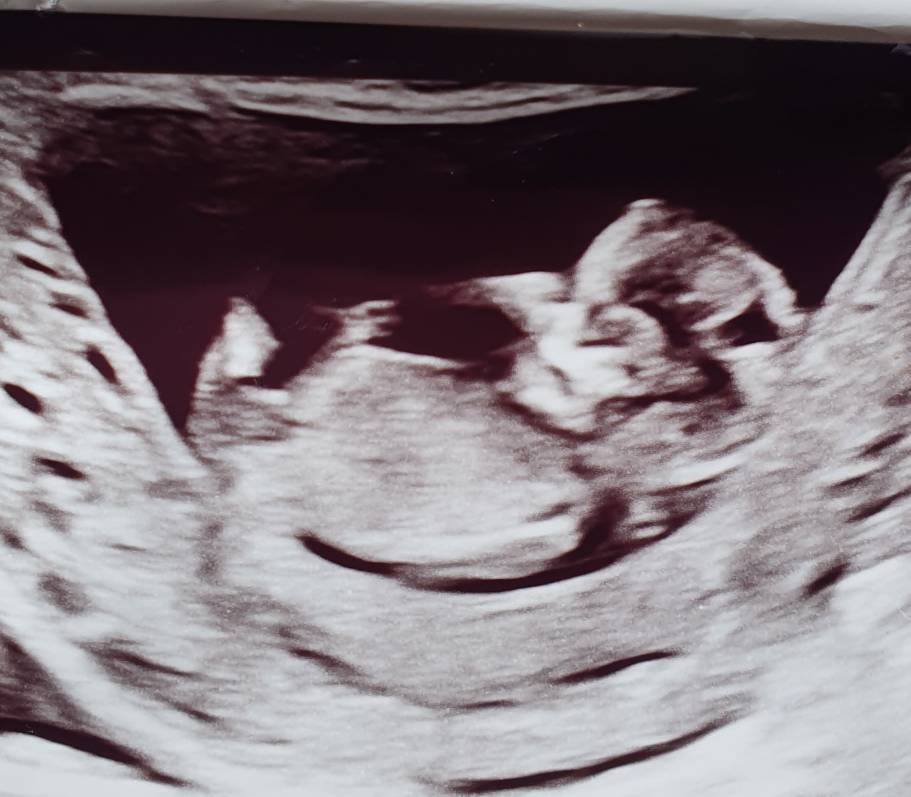

Can anybody give a guess on this.. Any nub is visible??I can't see anything. Verymuch excited to know what i am having

I'm afraid the nub isn't captured here - do you have any other shots?

Can you have a look at these pictures, any chance for a guess?? Thank you so much for your help[emoji3059]Attachment 43297Attachment 43300

The top pic looks boy but the bottom looks girl. I can't pin it down on the basis of these, sorry.